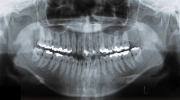

日本矯正歯科学会専門医課題症例(第6症例)

カテゴリー:Class Ⅲ (抜歯症例)

出題基準:大臼歯関係がclass Ⅲで、少なくとも前歯部が反対咬合または切端咬合で、ANB 0度以下が望ましい。条件は第5症例と同じだが、こちらは抜歯して治療して良い。